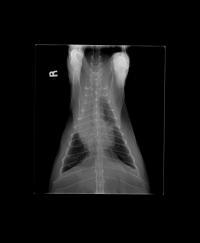

cardiomyopathy